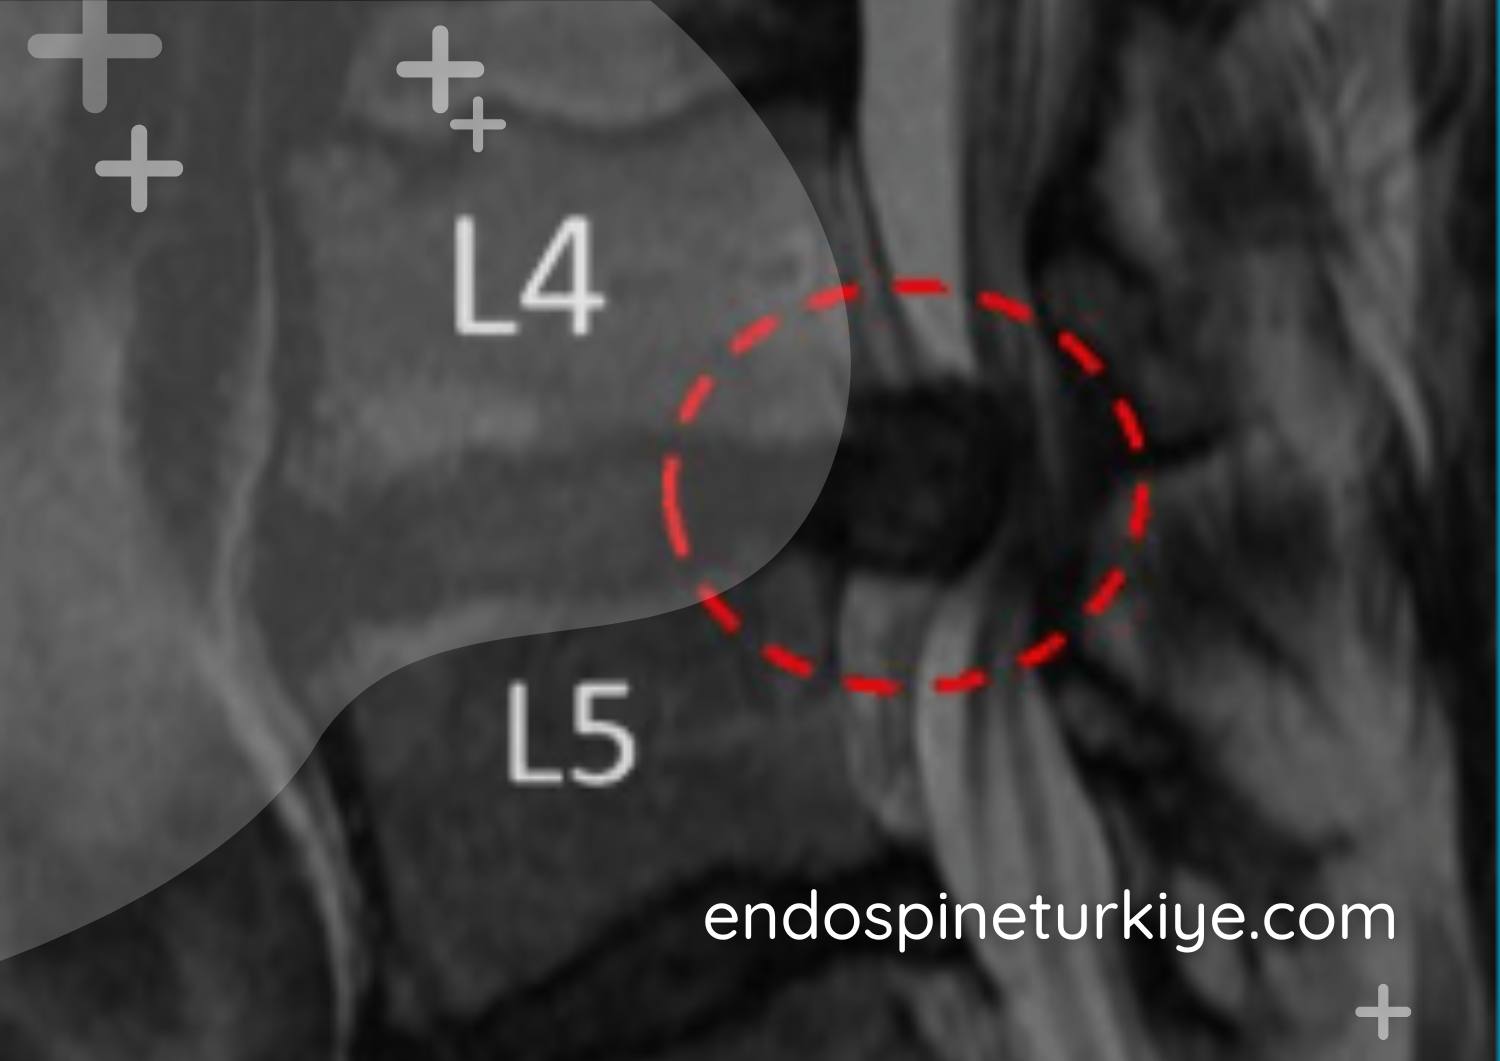

Tam kapalı dar kanal ameliyatı öncesi MR - kanal darlığı görüntüsü Ameliyat Öncesi

Tam kapalı endoskopik dar kanal ameliyatı sonrası MR - dekompresyon sonucu Ameliyat Sonrası